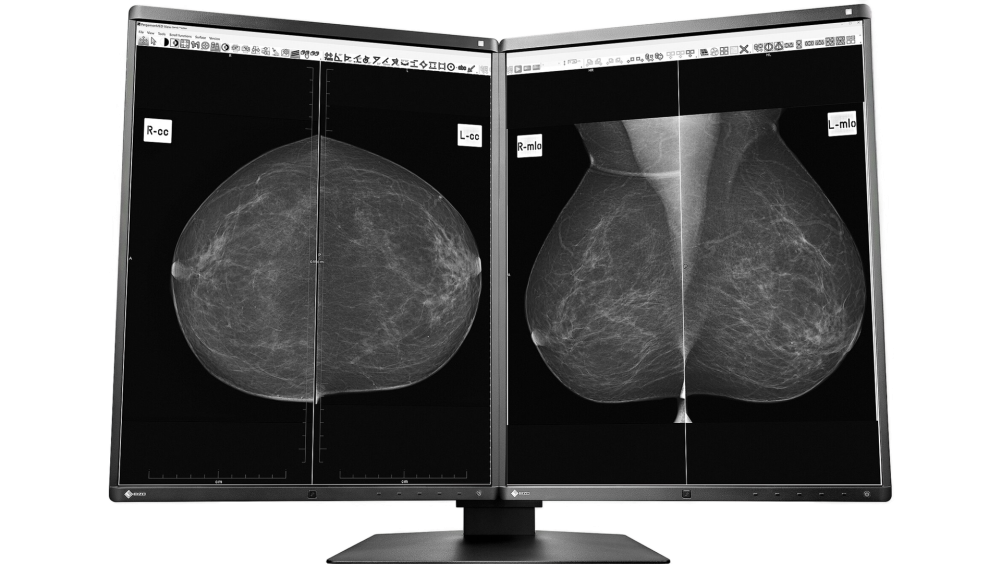

Die Röntgendarstellung der weiblichen Brust (Mammographie) wird in unserer Praxis auf einem Festkörperdetektor (CCD) registriert und in digitaler Form an unser Bilddatennetz weitergegeben. Die digitale Speicherung der Bilder gewährleistet, dass auch nach Jahren noch Kopien oder Bildvergleiche in Originalqualität möglich sind. Die Auswertung erfolgt an einem hochauflösenden Multimonitor-System.

Monitor EIZO Radiforce GX560